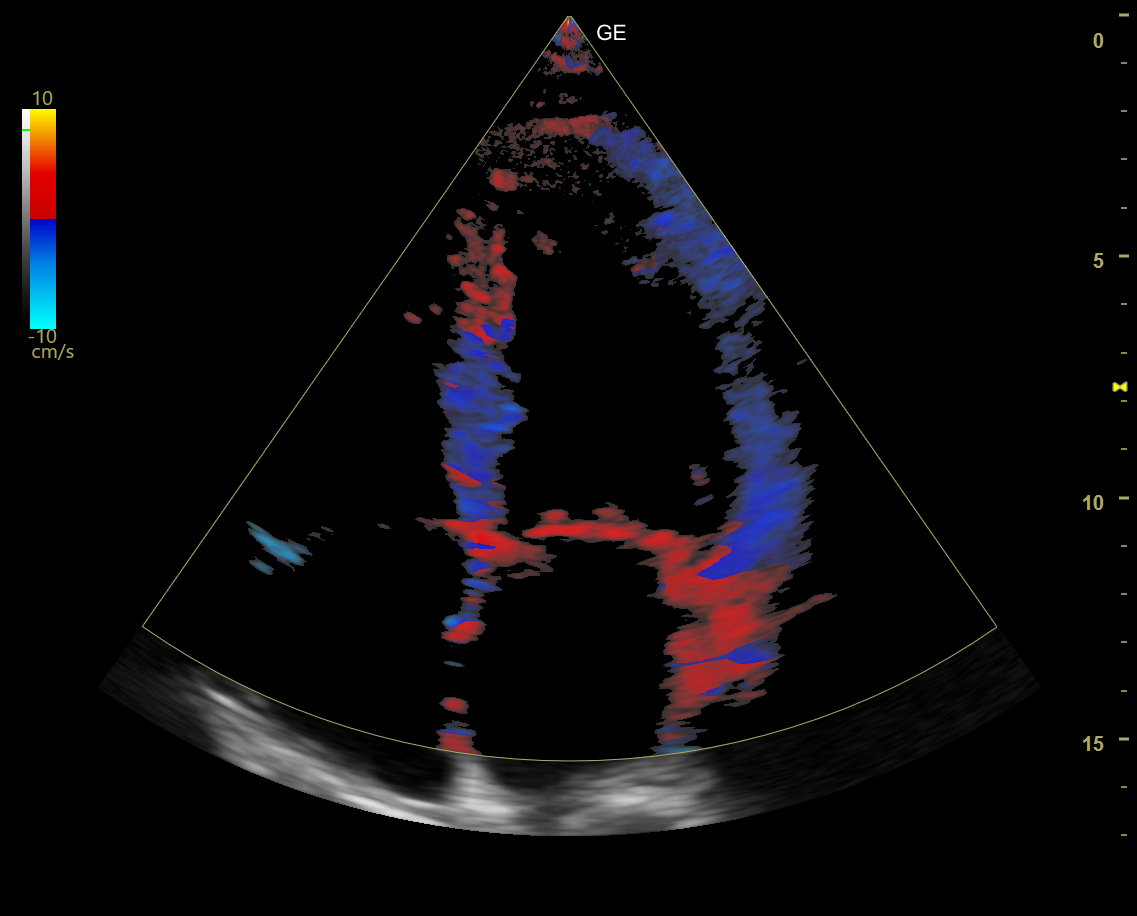

查看完整图像 超音频多功能图像系统 弗尼泽: 通用电气医疗 分类: 超声造影 水平标签 描述 凡尔赛那平衡是一个多功能生态系统,用于完成腹部检查、产科工程、口腔、肌肉、血管、泌尿、儿科和心脏病的检查。 Av和un设计工效学-现代、环保的成人能力-卓越的稳定性-诊断、快速、精确、分散和功能变化: 乳房护理/甲状腺生产力-分析模块,特别是在不同类型的系统中 B-流量-独立于生态技术的多普勒利用率评估血管结构 自动IMT-网络媒体自动管理模块 针识别-生物程序的虚拟化模块 自动EF-分析心脏变形的仪器,用于分析心室破裂的结石 Mod de analiză4DVizaliza toate cele 3 planuri ale structurilor Anomologie,av–and Utiliteîn specialîn aplicațiile de Occomaticăi de ginecologie 想象临床 查看完整图像 查看完整图像 查看完整图像 查看完整图像 德斯卡ă 描述: 韦尔萨纳兄弟天平 韦尔萨纳兄弟家族 教育 通用平台是一个可持续发展的教育支持平台,它是一个可持续发展的生态系统的应用平台,它是一个信息产业的发展平台,也是一个医疗实践的平台,在Versana ecografele中,阿替卡因和阿替卡因是一种具有丰富经验的药物。 特别是注册简单的VersanaClub depăeșeșe Barirele de timpși spași uneșutilizatori de ecografe Versana pentru联合国医疗卫生标准法案。 联邦登记局链接:https://www.versanaclub.net/ 视频 凡尔萨纳平衡:胜任。有效率的实际的 Versana Balance视频:胜任。有效率的实际的 特别条款: ATI 心脏病学 奇鲁吉将军酒店 内分泌学 家庭医学 麦地那 内科医生